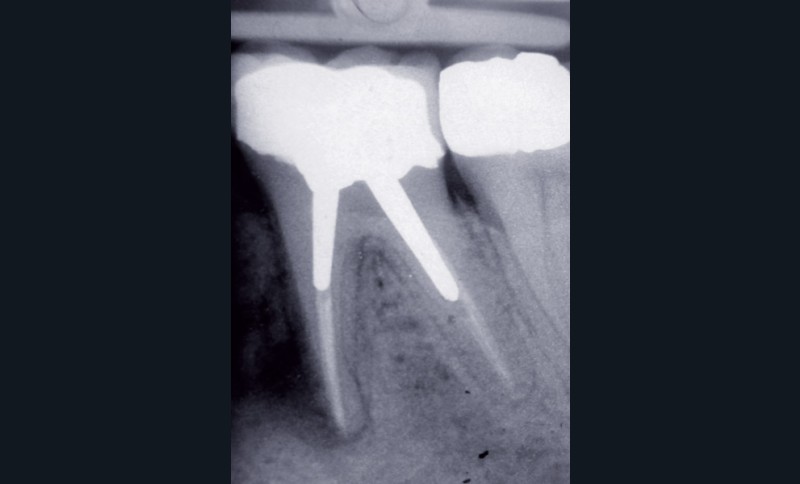

Dans un environnement parodontal sain, la chronologie des traitements conservateurs suite à la pathologie carieuse serait la suivante : le traitement endodontique de première intention, le retraitement endodontique et la chirurgie endodontique, voire l’amputation radiculaire. En cas d’échec, l’alternative implantaire pourra être envisagée (fig. 1).